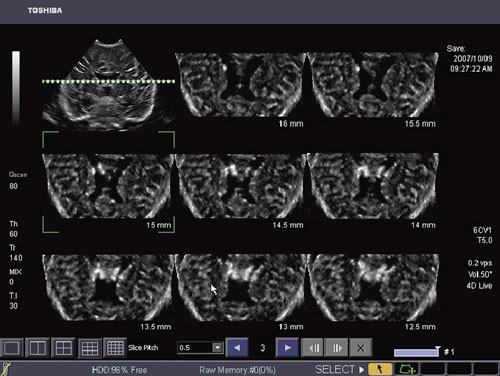

一般的には,MPR(multi planer reconstruction)は収集したボリュームデータから直交3断面を同時に表示する手法であるが,腹部領域において,例えば,肝腫瘍のような充実組織内の病変部を多面的に観察する場合には本手法が有用である。Multi Viewはこの手法をさらに発展させた機能で,CTスキャンで定着している一定間隔でスライスして得られた複数の断面を同時に表示することができる。

例えば,病変部を含む関心領域のボリュームデータを収集し,Multi Viewを使って病変部の複数のスライス像を同時に表示すると,病変部の広がりだけでなく,形態の空間的な変化を連続的に観察することが可能になる。また,小児頭部のようにスキャンのウインドウが限られるようなケースであっても,Multi Viewで任意のスライス断面を連続的に表示することができるため,これまでは観察が困難であったビューからも詳細な情報を得ることが可能となる(図3)。

さらに,Single Sweepモードを併用することで,高密度なボリュームデータ収集が簡便になるとともに,スライス方向を任意に変更しても常に高精細な断層像を表示することができる。MPRやMulti Viewで表示される断層像は,ダイナミックレンジやガンマカーブといった階調処理を2Dから継承しており,通常の2D像と同様な画質で表示することで検査者にシームレスな検査環境を提供している。 |

図3 Multi Viewによる小児頭部の水平断面像 |